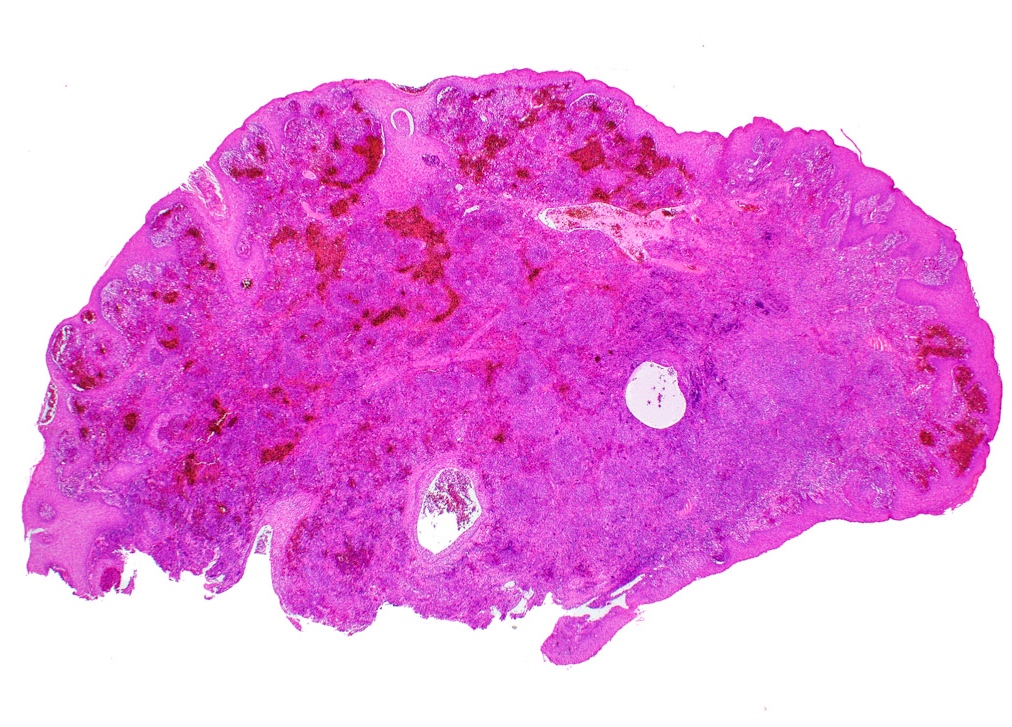

The above biopsy was taken from the posterior dorsal tongue at the midline. What is the microscopic pattern of the epithelium called?

1. Pseudoepitheliomatous hyperplasia

2. Squamous cell carcinoma

3. Squamous ductal metaplasia

4. Verrucous carcinoma

Practice answer #1

A. Pseudoepitheliomatous hyperplasia. When combined with the clinical information / photograph, the overall diagnosis of this case is median rhomboid glossitis, which is a particular diagnosis made in a patient with a red patch on the middle portion of the posterior dorsal tongue. The epithelium often shows elongated, bulbous shaped rete ridges (pseudoepitheliomatous hyperplasia) and superficial candidal colonization, as highlighted here by a PAS stain. Answer B is incorrect because the epithelium does not show significant atypia or detached islands of invasive epithelium. Answer C is incorrect because there are no salivary ducts pictured above; however, squamous ductal metaplasia may be seen in association with pseudoepitheliomatous hyperplasia in a setting of necrotizing sialometaplasia, a condition most often diagnosed on the hard palate. Answer D is incorrect because although the epithelium is bulbous and hyperplasic, a prominent verrucoid surface architecture and keratin clefting are not identified.